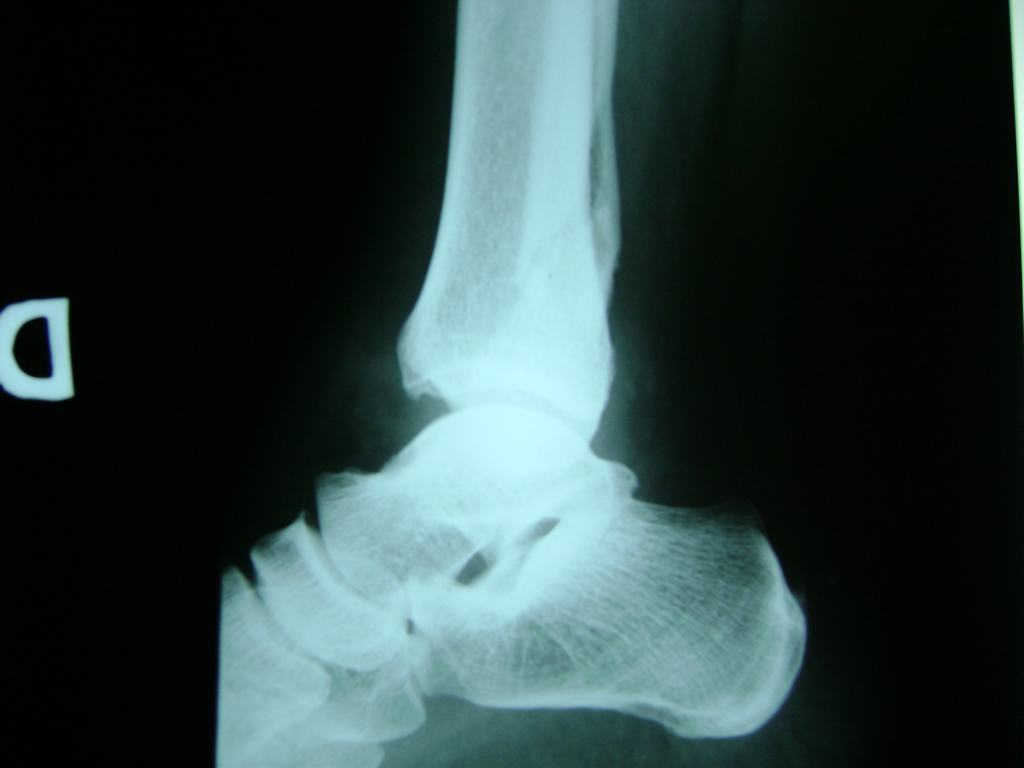

Una fractura de tobillo es la rotura de uno o más de los huesos del tobillo. Estas fracturas pueden ser:

- Parciales (el hueso está sólo parcialmente fisurado, no del todo).

- Completas (el hueso está perforado y está en 2 partes).

- Producirse en uno o ambos lados del tobillo.

Algunas fracturas de tobillo pueden requerir cirugía si:

- Los extremos de los huesos están desalineados entre sí (desplazados).

- La fractura se extiende hasta la articulación del tobillo (fractura intra-articular).

- Los tendones o ligamentos (tejidos que sujetan los músculos y los huesos entre sí) están rotos.

Cuando se necesita cirugía, es probable que esta implique el uso de clavijas de metal, tornillos o placas para sostener los huesos en su lugar mientras la fractura se consolida. Los elementos de soporte pueden ser temporales o permanentes.